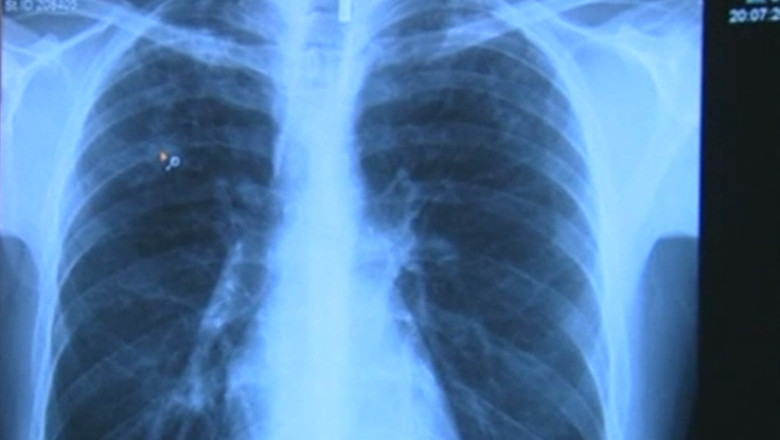

„Am simțit că slăbesc foarte tare, tuşeam noaptea extraordinar de mult şi transpiram. Am fost nevoit să merg la medicul de familie, medicul de familie mi-a dat să fac o radiografie şi la radiografie a reieşit asta”, povestește el.